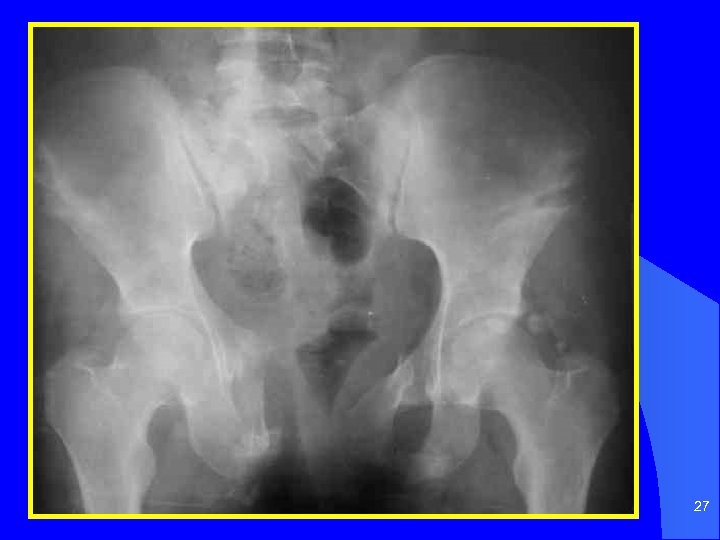

27